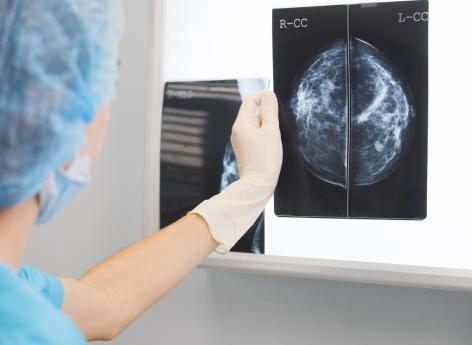

Cancer du sein : la glace peut éliminer une tumeur sans chirurgie

La cryoablation, une technique qui consiste à mettre du froid extrême sur la tumeur pour tuer les cellules cancéreuses, vient d’obtenir de très bons résultats pour le cancer du sein.

Traiter le cancer du sein par le froid, c’est ce que propose une nouvelle étude du Memorial Sloan Kettering Cancer Center de New York présentée lors du congrès annuel de la Society of Interventional Radiology, aux États-Unis.

Cancer du sein : le froid pour tuer les cellules cancéreuses

La technique utilisée s’appelle cryoablation. Concrètement, après avoir localisé la tumeur, les médecins - via des sondes - l'entourent d'un froid intense afin d’y former une boule de glace. Ce qui tue les cellules cancéreuses.

Lors de leurs travaux, les scientifiques ont suivi 60 patientes qui ont fait une cryoablation, soit parce qu’elles ne pouvaient pas bénéficier d’une opération chirurgicale, soit parce qu'elles l’avaient refusée après consultation avec un chirurgien (en raison de leur âge, de problèmes de santé, ou de traitements qu’elles avaient en parallèle…). La taille des tumeurs allait de 0,3 cm à 9 cm, avec une taille moyenne de 2,5 cm.

L'intervention a été réalisée en ambulatoire sous anesthésie locale ou sous sédation minimale. Il y a eu deux cycles, sur une même journée, de gel et dégel. Le premier durait 5 à 10 minutes, suivies de 5 à 8 minutes de décongélation. En tout, la procédure durait en moyenne trente minutes.

"Pendant longtemps, la cryoablation a été utilisée pour traiter les tumeurs du sein plus petites (classées comme inférieures à 1,5 cm), mais cette étude montre que la cryoablation peut également être efficace pour les patientes présentant des tumeurs plus grosses", explique Yolanda Bryce, radiologue au Memorial Sloan Kettering Cancer Center, l’une des auteures de l'étude, dans des propos rapportés par le New York Post.

Cryoablation : seules 10 % des patientes ont eu une récidive

En effet, les résultats des chercheurs sont encourageants : associée à de l’hormonothérapie et à de la radiothérapie, la cryoablation a permis de détruire 100 % des tumeurs. De plus, pendant les seize mois de suivi, seules 10 % des participantes ont eu une récidive de cancer.

"Lorsqu'elles sont traitées uniquement par radiothérapie et hormonothérapie, les tumeurs finissent par réapparaître, indique Yolanda Bryc. [Notre découverte] d’un taux de récidive de 10 % est incroyablement prometteur."

La technique est moins invasive qu’une opération chirurgicale, mais elle peut entraîner des brûlures de la peau. Toutefois, d’après les auteurs, les femmes qui ont connu cet effet secondaire, ont été traitées grâce à une pommade et n'ont pas gardé de séquelles.

"La chirurgie reste la meilleure option pour l'ablation d'une tumeur, mais des milliers de femmes ne peuvent pas subir d’opération pour diverses raisons, indique Yolanda Bryce. Nous espérons que nos résultats pourront donner de l'espoir à davantage de femmes dans leur parcours de traitement."

En France, il y a eu 61.214 nouveaux cas de cancer du sein en 2023. Cela représente une progression de 0,3 % depuis 2010, selon le Panorama des cancers en France - édition 2023. Il s’agit des tumeurs malignes les plus fréquentes chez les femmes. Toutefois, dépisté tôt, c’est un cancer de bon pronostic.